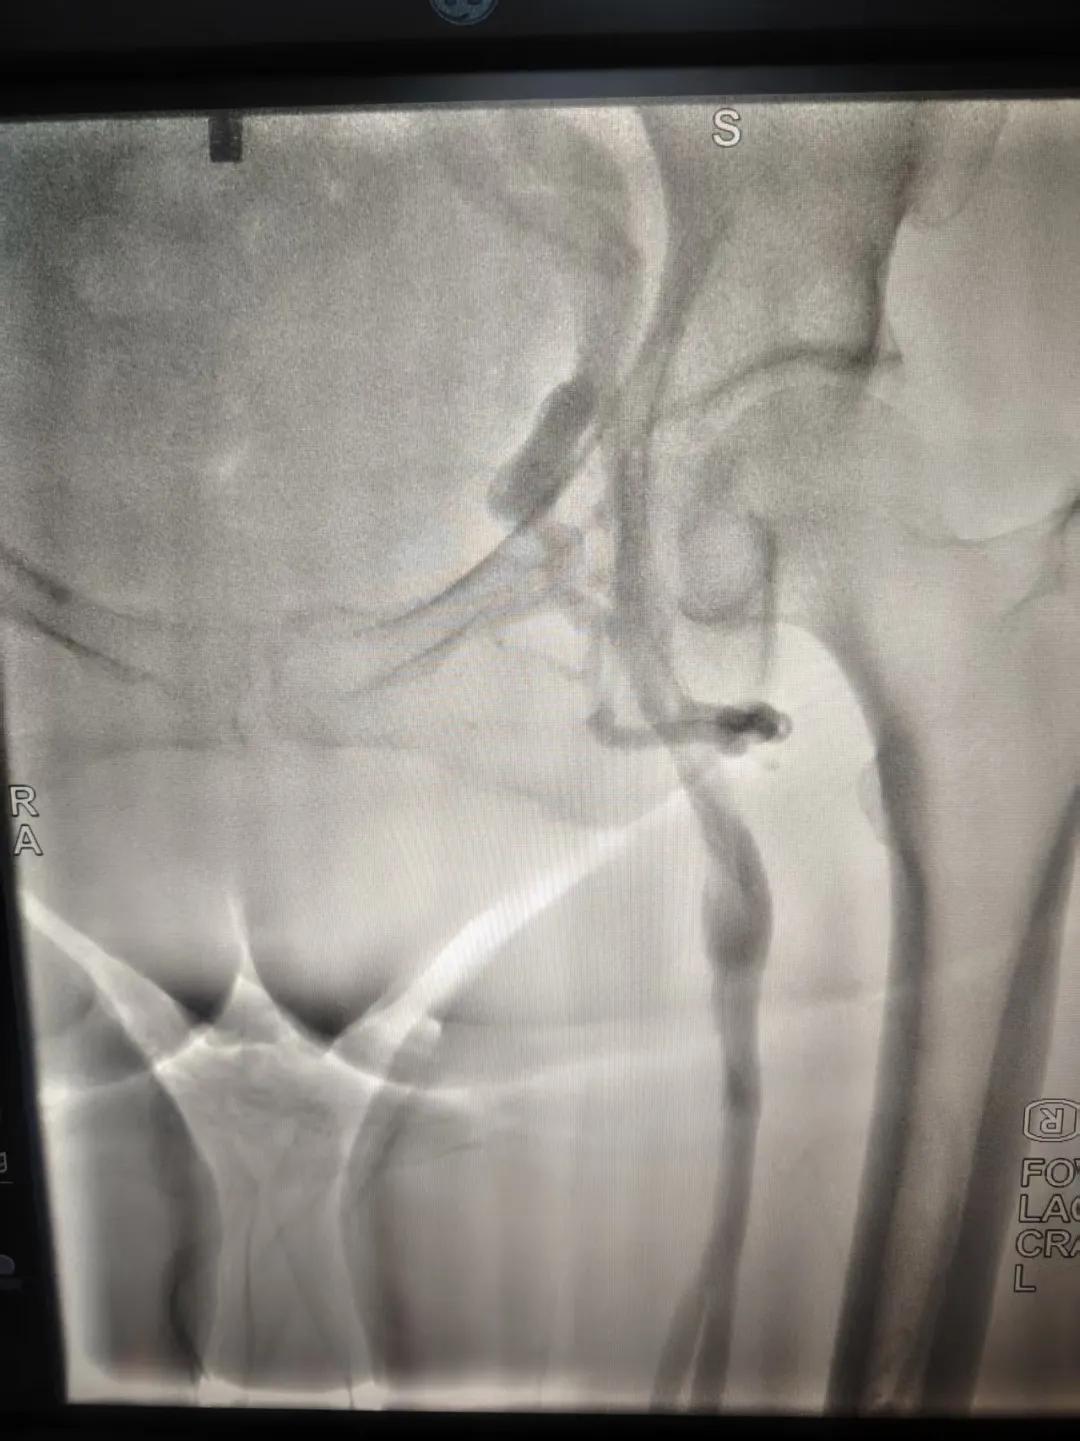

該患者,中年女性,左下肢反復(fù)腫脹、疼痛多年就醫(yī),未明病因。門(mén)診就診,經(jīng)血管外科副主任周創(chuàng)業(yè)評(píng)估病情后,為該患者門(mén)診行下肢靜脈造影,造影結(jié)果示:左髂靜脈周圍側(cè)枝形成,左髂靜脈壓迫綜合癥。明確診斷后將擇期介入手術(shù)治療。

下肢靜脈造影是診斷下肢靜脈病變(如深靜脈血栓、靜脈曲張、靜脈功能不全等)的“金標(biāo)準(zhǔn)”。靜脈造影可直觀顯示受壓部位、狹窄程度及側(cè)支循環(huán)形成情況,明確診斷與定位,指導(dǎo)治療決策,以及介入治療規(guī)劃,血栓評(píng)估,在復(fù)雜病例或介入治療中造影具有優(yōu)勢(shì)。